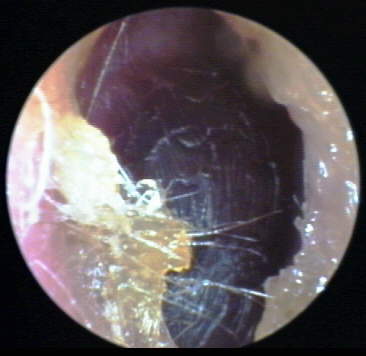

EXTERNAL AUDITORY CANAL

TYMPANIC MEMBRANE / MIDDLE EAR